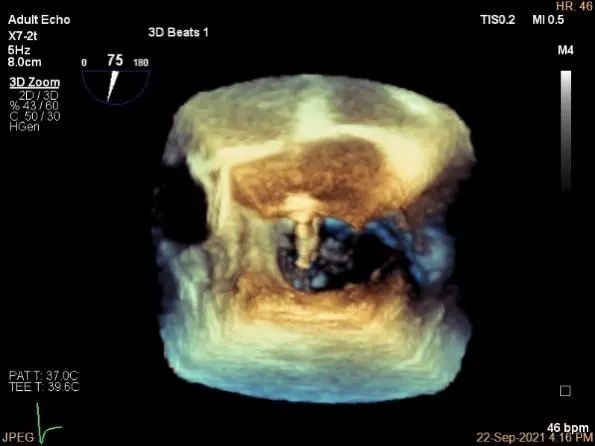

术中超声

3D:P1区脱垂并腱索断裂,部分AC受累,Width:11.4mm

计算前叶捕获长度9mm,后叶捕获长度7mm。

夹子夹闭后,未见明确残余分流

3d确认夹子位置在P1区